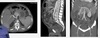

Homem, 60anos, dor torácica e abdominal de forte intensidade há 2 horas.

Dissecção de aorta abdominal, com artéria renal direita oriunda da luz falsa.